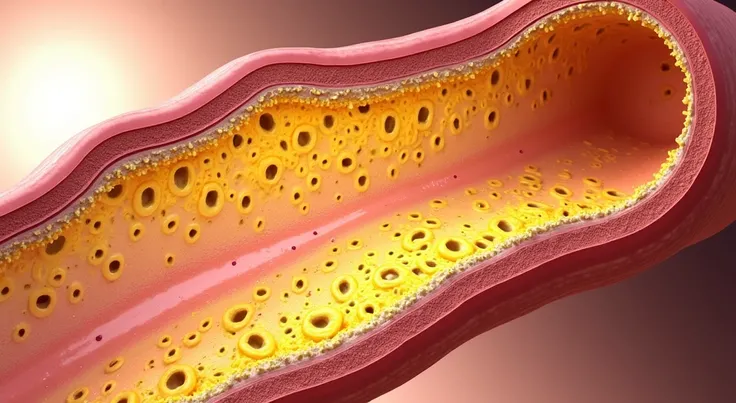

Pictures of swollen thyroid gland in neck, Use a Canon EOS 5D Mark IV with a 24

pictures of swollen thyroid gland in neck, Use a Canon EOS 5D Mark IV with a 24-70mm f/2.8 lens. Settings: ISO 100, aperture f/8, and shutter speed 1/125s to capture a sharp, vibrant image with a wide depth of field.

pictures of swollen thyroid gland in neck